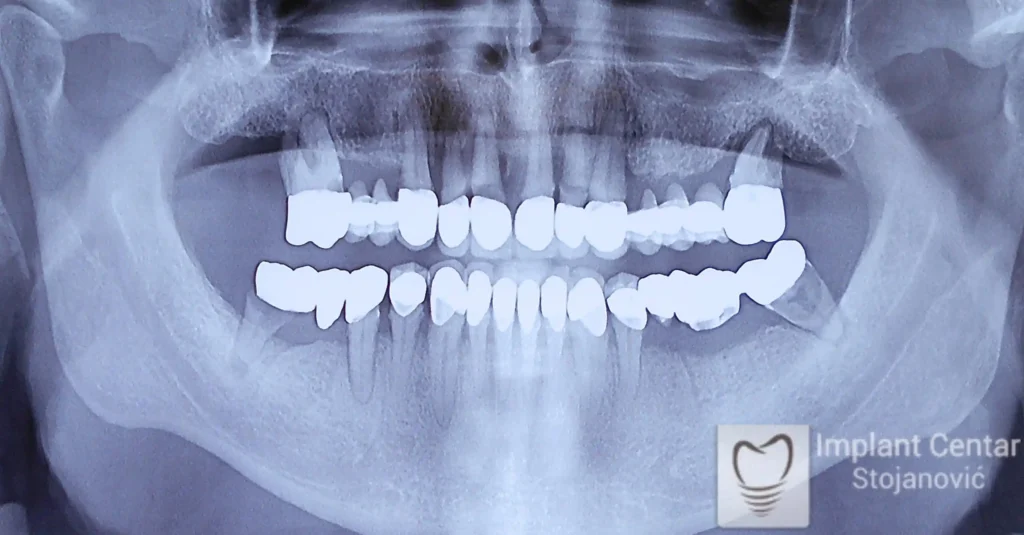

Pacijentkinja je došla sa dotrajalim mostovima i preostalim zubima loše biološke vrednosti, dok su bezubi prostori bili prisutni u gornjoj vilici sa desne strane i  u donjoj vilici sa leve strane. Nakon detaljnog kliničkog pregleda i analize snimaka, izvršeno je vađenje svih zuba i ugradnja optimalnog broja dentalnih implantata.

Već tri dana nakon operacije pacijentkinja je zbrinuta privremenim krunicama, kojima je bila oduševljena jer su odmah omogućile funkciju i estetiku. Nakon perioda oseointegracije izrađene su definitivne cirkonijum-keramičke krunice, čime je postignuta maksimalna estetika, funkcija i vraćeno samopouzdanje. Pacijentkinja je presrećna postignutim rezultatom.